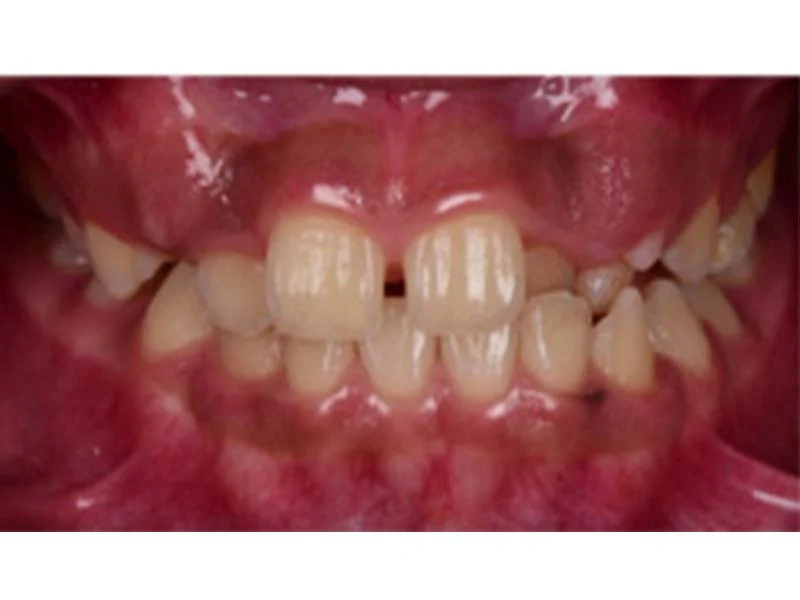

兒童在換牙期出現前牙錯咬時,若能儘早使用簡單的斜面咬合板治療, 百分之90以上的錯咬改正都可得到很好的效果,費用少,且時間短, 若沒在適當時間改善前牙錯咬,會因錯咬影響或限制小朋友顎骨的發育, 提前做一些處理,可以讓小朋友恢復正常的咬合關係, 也會減少將來矯正治療的難度。